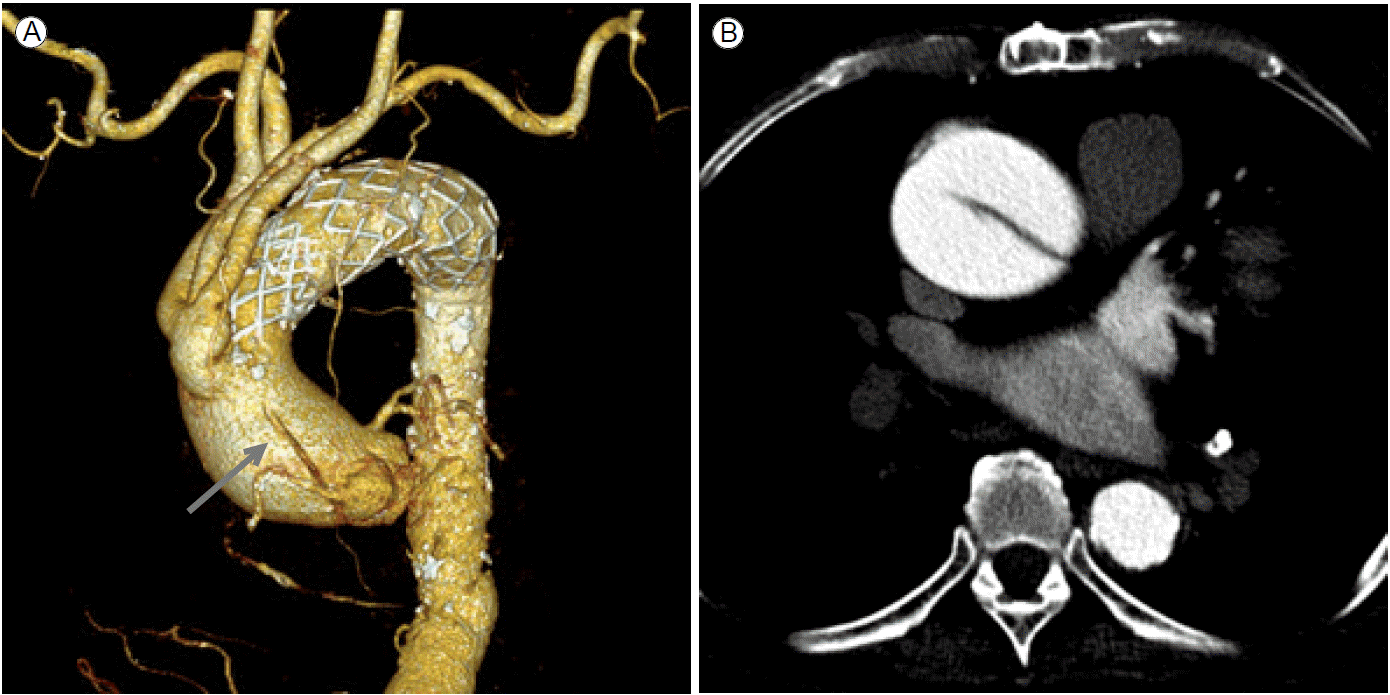

경우에 따라서 근위부 봉인부위의 길이가 충분하지 않을 경우 좌쇄골하동맥을 넘어서 스텐트 그라프트를 시술할 수도 있는데 이때 주요 분지혈관의 우회술이 필요할 수도 있다(Fig. 2). Ishimaru [10]는 근위부 봉인부위의 위치에 따라 5개의 구역으로 나눠 구분하였다(Fig. 2A).

만약 zone 0/1에 스텐트 그라프트를 시술한다면 시술 전 완두동맥이나 좌총경동맥을 좀 더 근위부 쪽으로 우회술하여 근위부 봉인부위를 충분히 확보한 후 스텐트 그라프트를 시술하게 된다(Fig. 3). 우회술 없이 좌쇄골하동맥을 막는 것에 대해서는 아직 논란이 여지가 있는데 일반적으로 시술 전 두경부 혈관들을 충분히 검사한 후 재관류 여부를 결정하게 된다. 수술적 방법은 다양하다.